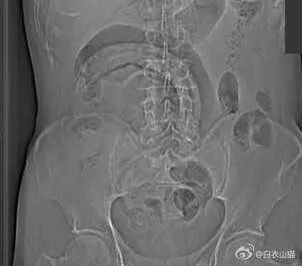

上面是近年医院里的一个病人,也是乙状结肠新鲜穿孔。医生给他开腹手术,从腹腔里取出来的5条泥鳅和一条黄鳝。

该病人提供的病史,是自己把活泥鳅和黄鳝生吞下去所导致。其实,医生一看泥鳅和黄鳝的颜色以及肠穿孔的部位,就知道怎么回事了。